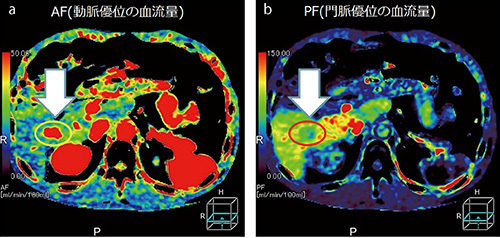

また、Aquilion ONE/Global Standard Editionでは、インプラントなどの金属アーチファクトを低減させる“SEMAR(Single Energy Metal Artifact Reduction)”の効果が指摘できる。藤田臨床顧問は、「SEMARによって、これまでアーチファクトで診断ができなかった部位でも読影が可能になり、特に整形外科領域では診断の幅が広がりました」と述べる。さらに、Aquilion ONE/Global Standard Editionでは、面検出器を用いた連続撮影によるボディパーフュージョン撮影が可能になっている。藤田臨床顧問は、「Aquilion ONE/Global Standard Editionでは、16cm幅でパーフュージョン撮影が可能になり、ほぼ肝臓全体をとらえることができます。さらに、CTパーフュージョンでの課題だった被ばく線量についても、AIDR 3Dによって大きく削減することが可能です。パーフュージョン撮影では、かなり線量を落としても、造影剤によってSNRが向上します。これによって、従来のダイナミックスタディ4相分と同等か、それ以下の線量での撮影が可能になると考えています」と期待する。

■症例2 TACE後治療効果判定:肝パーフュージョン